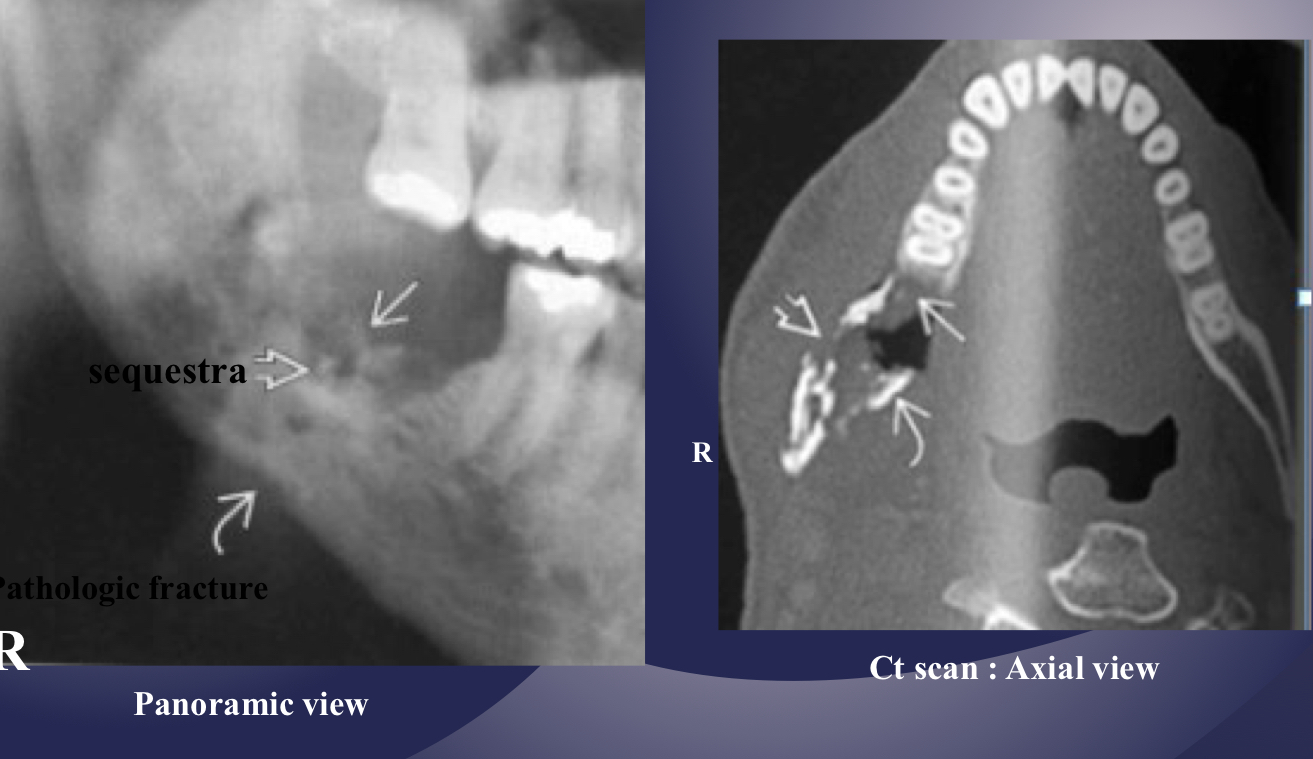

which osteomyelitis phase?

internal structure:

sequestration, sinus tract or fracture

acute

white and black arrow

which imaging is method of choice for seeing internal structure (sequestrea) of acute osteomyelitis?

CT/CBCT

what’s going on here?

what is going on here?

pathological fracture, facture on a compromised boone